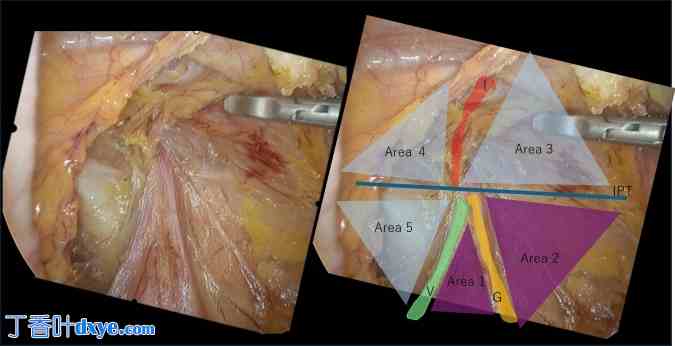

腹腔镜下腹股沟区视图中,基于由三个标志——下腹壁血管 (IEPV)、输精管 (VD) 和性腺血管 (GV)——以及水平穿过腹股沟外环的髂耻束 (IPT) 形成的“倒 Y 形”结构,可以识别五个解剖区域(图 1)。“梯形”区域(ToD)是应避免神经损伤的区域,它通过这个“五三角”网格  间接识别(图 1)。因此,开发一个能够自动识别 IEPV、VD 和 GV 的模型,或许有助于识别 ToD。

图 1

1.jpg

右侧腹股沟疝。基于下腹壁血管 (I)、输精管 (V)、性腺血管 (G) 和肠道 (IPT) 形成的“倒 Y 形”,可以识别出五个解剖区域。区域 1 和 2 可以通过这个“五角形”网格清晰地识别,因此可以识别为“灾难梯形”(ToD)。